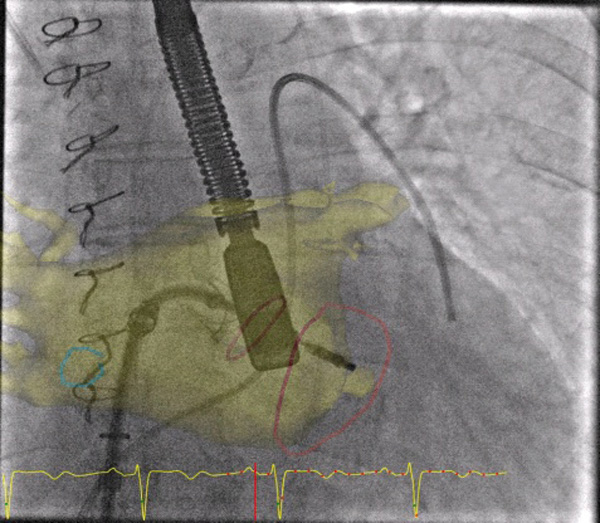

L’intervention consiste à introduire par la veine fémorale un cathéter qui sert de guide au dispositif dans la veine cave inférieure jusqu’à l’oreillette droite. Là, via une ponction au travers du septum inter-auriculaire, le médecin accède à l’oreillette gauche où il peut positionner le clip au-dessus de la valve mitrale, face au flux de la régurgitation mitrale. Le clip est alors placé exactement là où s’initie la fuite, entre les feuillets de la valve mitrale. La fermeture du clip permet de rapprocher les feuillets et de réduire la fuite. Lorsque le contrôle échographique indique un résultat satisfaisant, le clip est largué et le cathéter retiré. «?L’intervention est longue. Il faut compter environ quatre heures pour parvenir à attraper correctement deux feuillets asymétriques avec un clip symétrique, expliquent Adeline Guenat et Béatrice Toublanc, manipulatrices en électroradiologie médicale, qui jouent un rôle important dans l’intervention?: Nous nous chargeons de positionner le patient et le dispositif, qui doit rester parfaitement immobile et exactement à la même distance du cœur pendant toute la durée de l’examen. Une fois réalisée cette installation rigoureuse, le manipulateur est responsable pendant toute l’intervention du matériel spécifique et complémentaire.?»